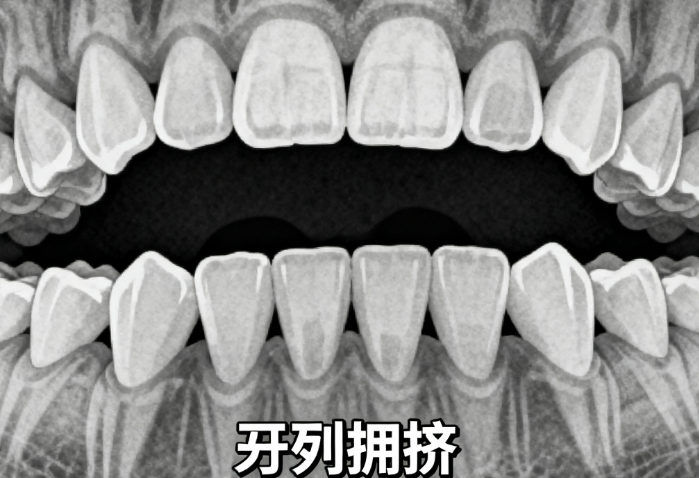

术前咬合状态是关键指标

若术前存在骨性反颌或下颌后缩等咬合紊乱,正畸治疗往往是手术的辅助手段。术前正畸可减少术后关节压力,例如通过调整牙齿位置重建咬合中心关系。